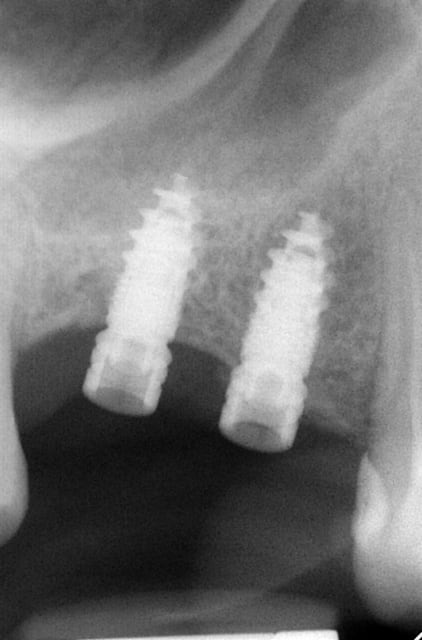

Pour ceux que ca interessent, et parce qu on a m a demandé des cas supplémentaires dans le sujet 23 implants rehabilitation totale, voici un autre cas d implantation immédiate avec la technique minimalement invasive et condensation grace aux forets.

Le patient a reçu un traitement il y a dix ans dans le maxillaire et dans le 4eme quadrant.Comme on peut le voir j´ai du extraire quelques dents au maxillaire: 35 37 et 45.

Le septum de la 37 a été foré avec un foret conique 3 faces.

J ai planté à 60 Ncm sans fracturer le septum.Juste après l opération , les prep caps en zircon ont été cémenté.La restauration définitive 34 jusqu` à 37 été fixé 2 semaines après l implantation avec implantlink (detax). Après un an, le bridge a été retiré facilement pour voir l´état de la gencive et faire une radio de contrôle.On la re ossifiction est satisfaisante et que la gencive "aime" le zircon.

Le bridge a ensuite été recémenté sans correction nécessaire du bridge.